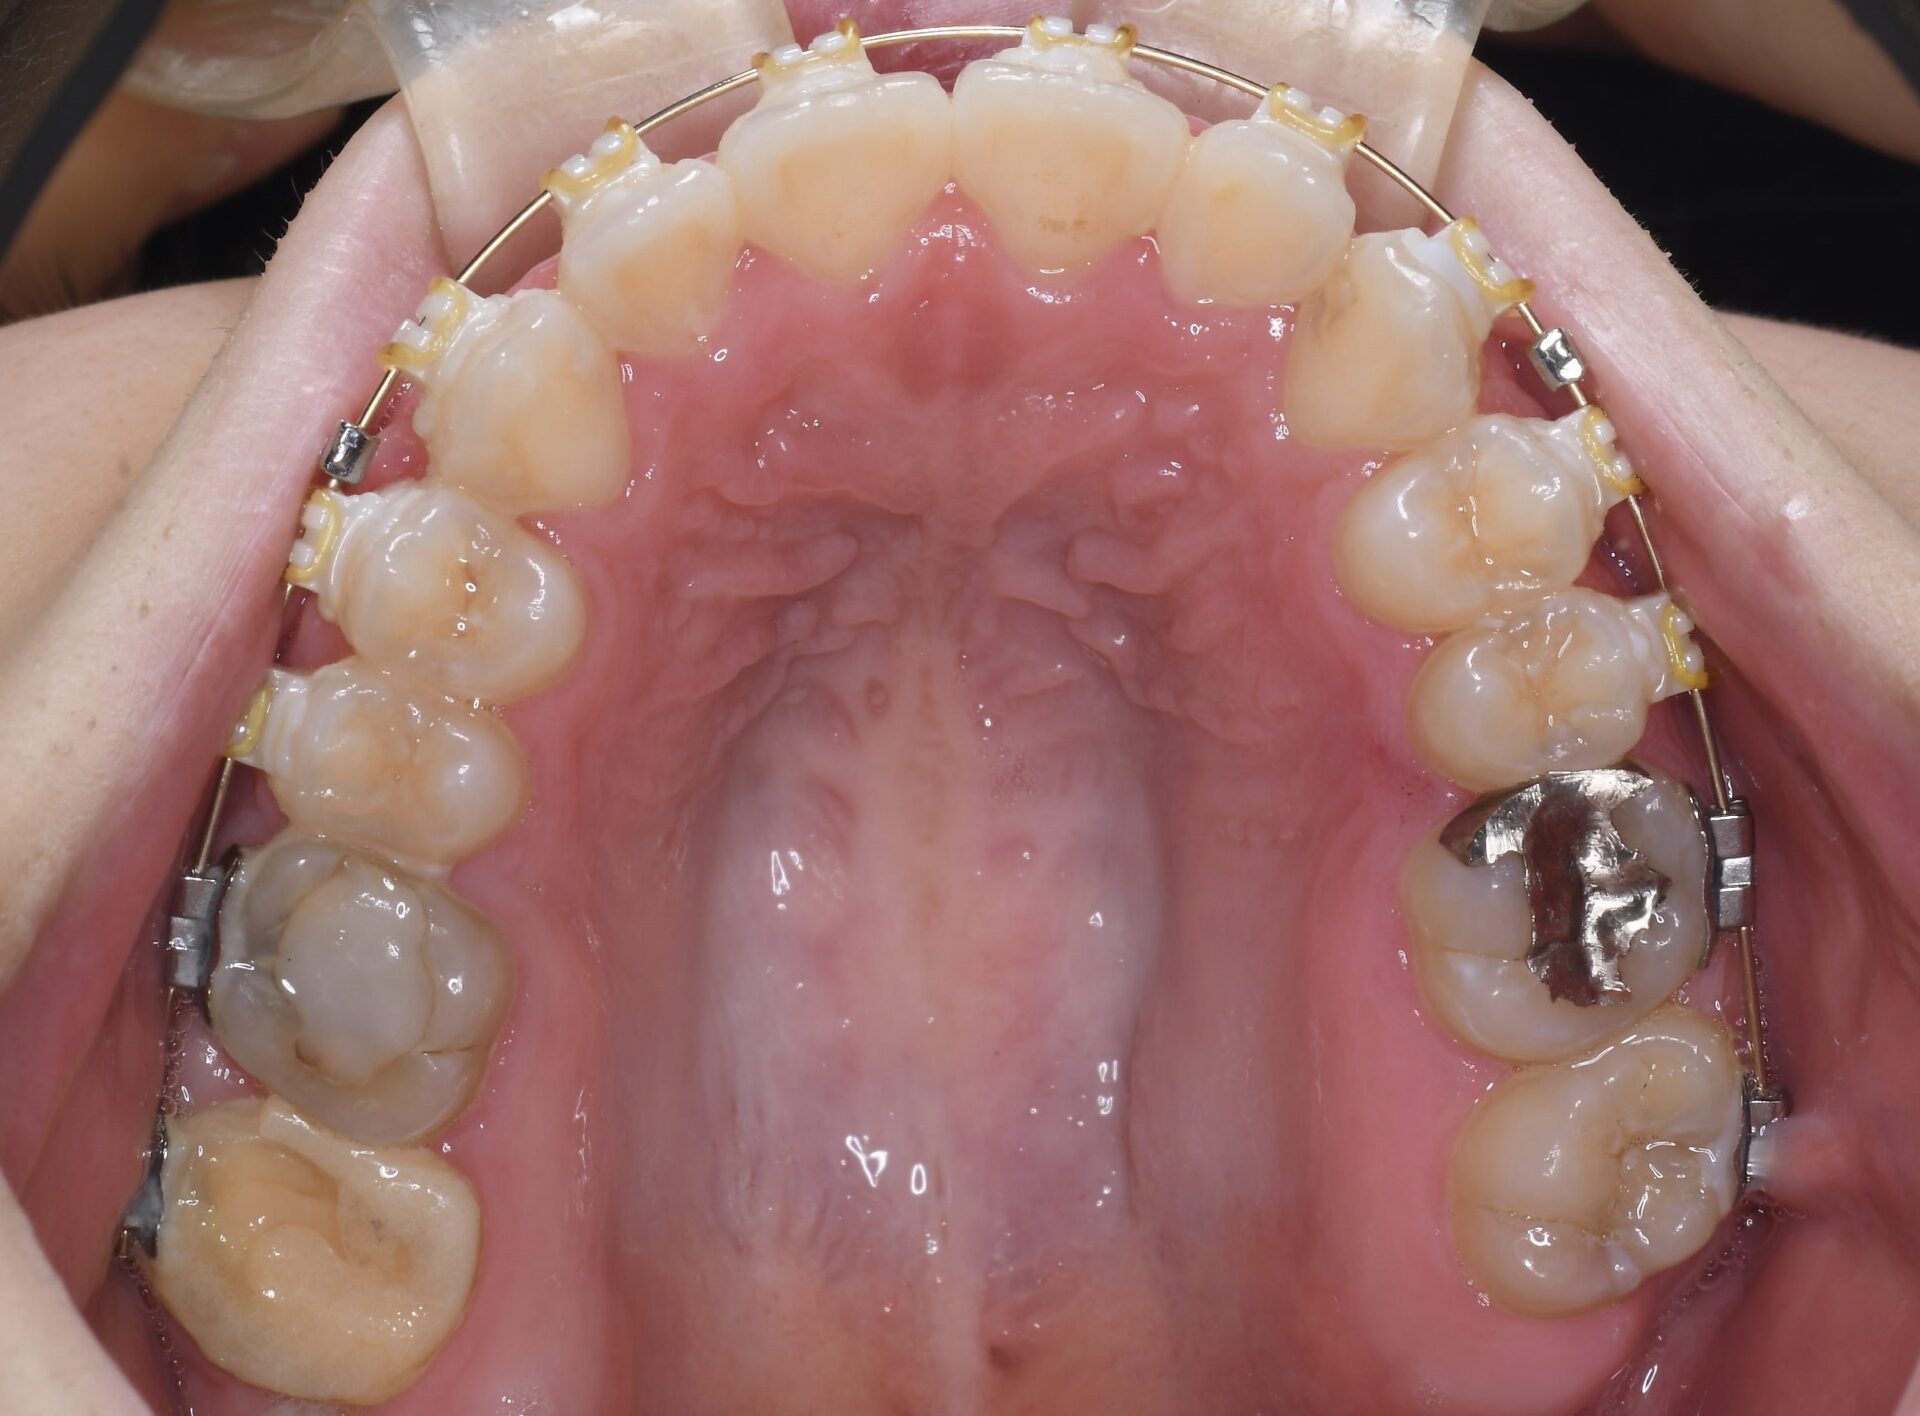

矯正治療スタート時(上顎)

臼歯でしか噛んでいないため20代前半にもかかわらず、すでに右上第1、第2大臼歯は神経の処置がされていた。